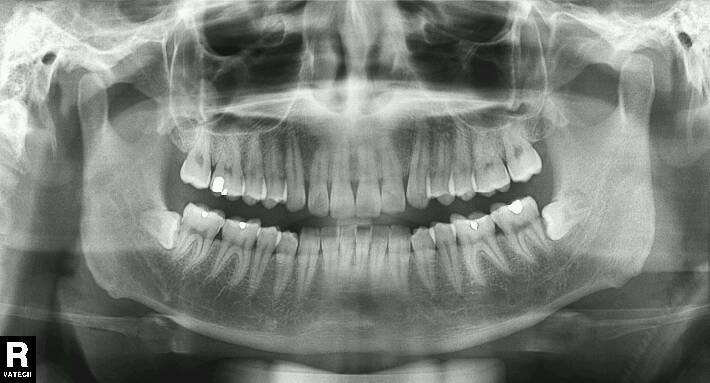

看到没,只有这样整整齐齐,根正苗也正,顺利长出来的智齿,才有可能逃过一劫。